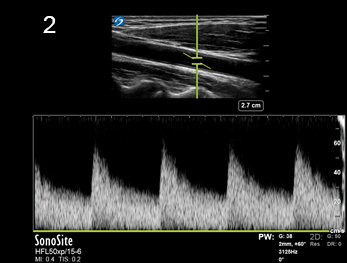

Aliasing Artifact PW Doppler Image